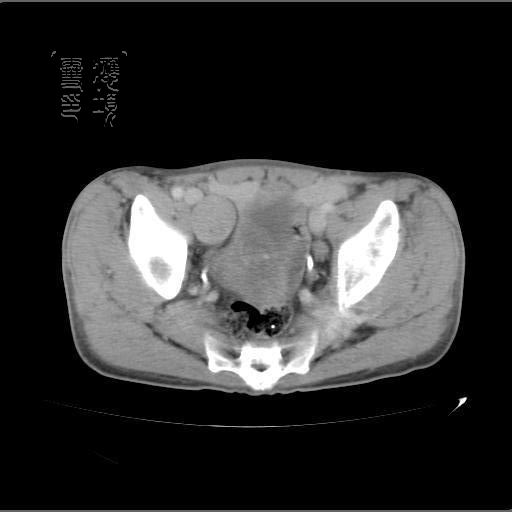

以下是引用dyqct在2007-4-20 20:51:00的发言:[br]考虑:1、右侧膀胱外上方实性富血管性肿瘤(神经鞘膜瘤?纤维瘤?巨淋巴结增生症?)[br] 2、请标识需要解释的地方。

以下是引用aa13877358820在2007-4-21 7:01:00的发言:[br]隐睾?